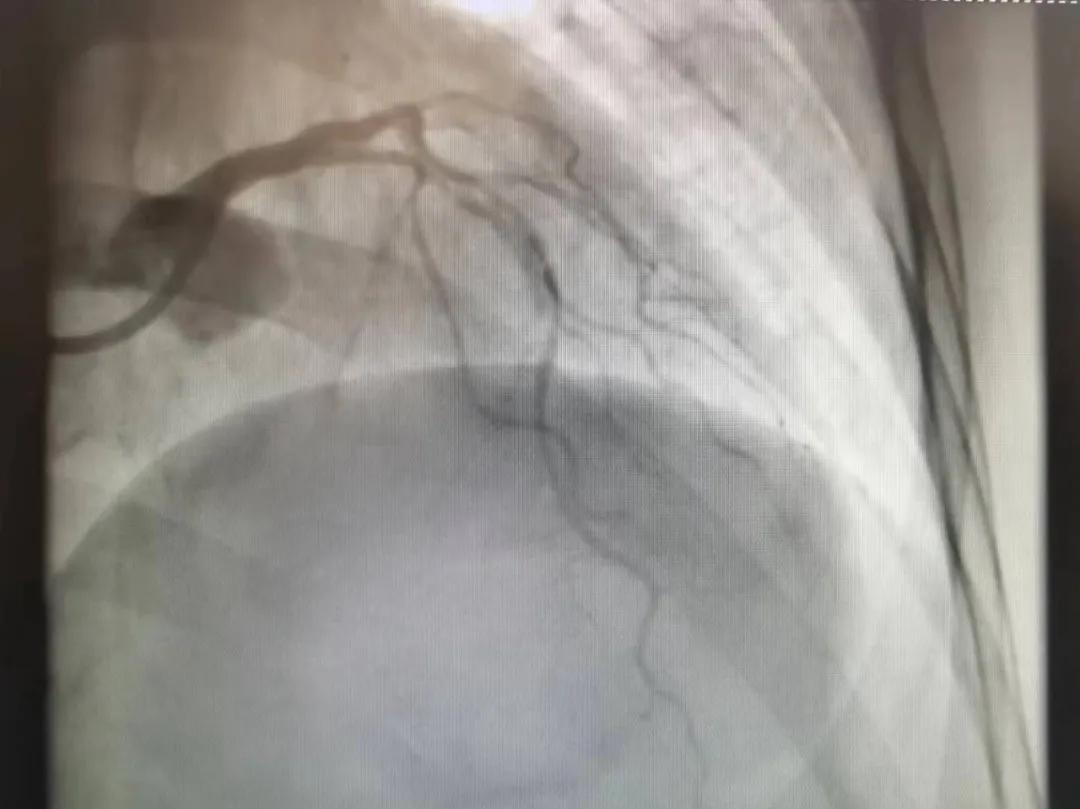

王瑾院長(zhǎng)和李慧新主任帶領(lǐng)介入團(tuán)隊(duì)充分評(píng)估,決定行前降支冠狀動(dòng)脈鈣化病變旋磨術(shù),術(shù)中應(yīng)用1.5mm旋磨頭,以15萬(wàn)-17萬(wàn)轉(zhuǎn)/分速度共對(duì)病變旋磨3次,累計(jì)旋磨時(shí)間60秒,后復(fù)查造影示鈣化明顯減輕,為后續(xù)操作創(chuàng)造了良好條件,隨后應(yīng)用預(yù)擴(kuò)張球囊、切割球囊再次處理病變,并順利植入支架1枚,復(fù)查造影顯示支架膨脹及貼壁良好,無(wú)夾層、血腫、慢血流等情況,手術(shù)順利完成?;颊咝g(shù)后無(wú)不適,胸悶、胸痛癥狀明顯緩解,順利出院。

術(shù)后